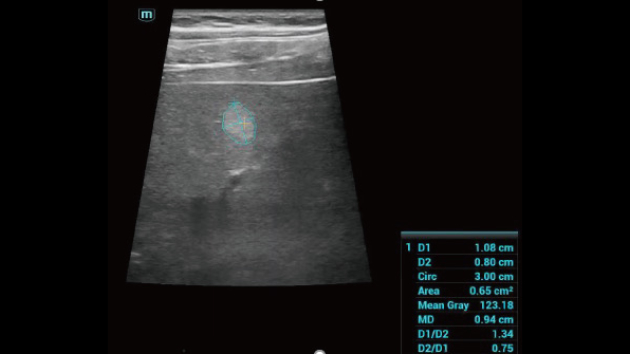

Comprehensive Imaging Solutions Powered by ZST+

The ZST+ platform is an extraordinary innovation, representing an ultrasound evolution. Transforming ultrasound metrics from conventional beam-forming to channel data based processing. It overcomes the traditional trade-off limitation among spatial resolution, temporal resolution and tissue uniformity, delivering exceptional image quality for infinite imaging solutions with non-stop improvements.